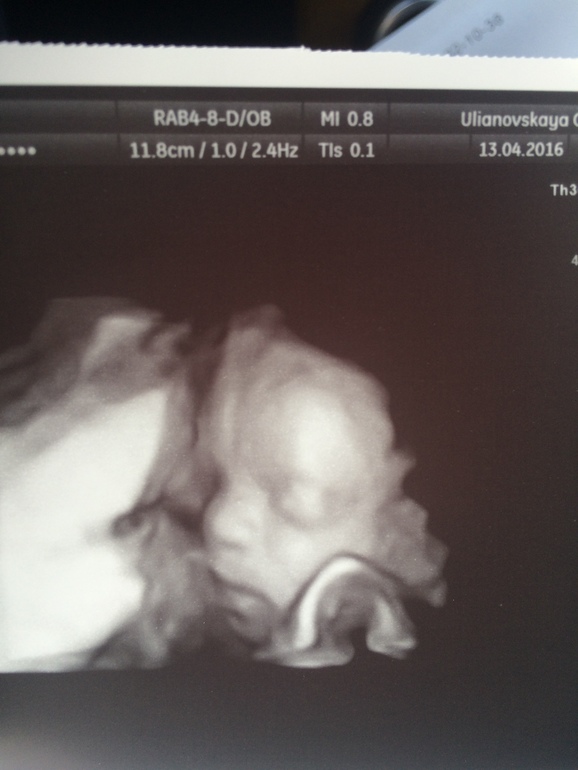

У меня вот такая де фотка в 23 недели

Сын в 23 нед..)